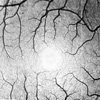

The ocular fundus (background of the eye, see fig. 1) offers the unique opportunity to visualize the blood vessel system in vivo. Scanning ophthalmoscopes such as the Rodenstock LSO® (fig. 2) deliver high–resolution dynamic image sequences at video frame rates which resolve vessels close to the size of the capillaries (fig. 3 foveal region).

The perfusion of the retinal blood vessels can be observed dynamically by means of an intraveneous application of fluorescent agents (e.g. fluorescine, ICG), the so–called retina angiograms. By means of a sophisticated registration process the indispensable eye movements—even sudden large saccades— are compensated to sub–pixel accuracy, see motion picture sequence (the moving frame demonstrates the compensated movements). The delay of the local arrival of the contrast agent bolus indicates the local distribution of the blood velocity. Appropriate color coding schemes yield functional images which offer a quick interpretation of the

Calibration of above functional images by distributed local measurements of the blood flow velocity (e.g. by laser doppler velocimetry) yields a further improvement. To achieve a correct spacial correlation between images and local measurements the images have to morphed on a sphere model of the eyeball which results in so–called ocular perfusion maps.